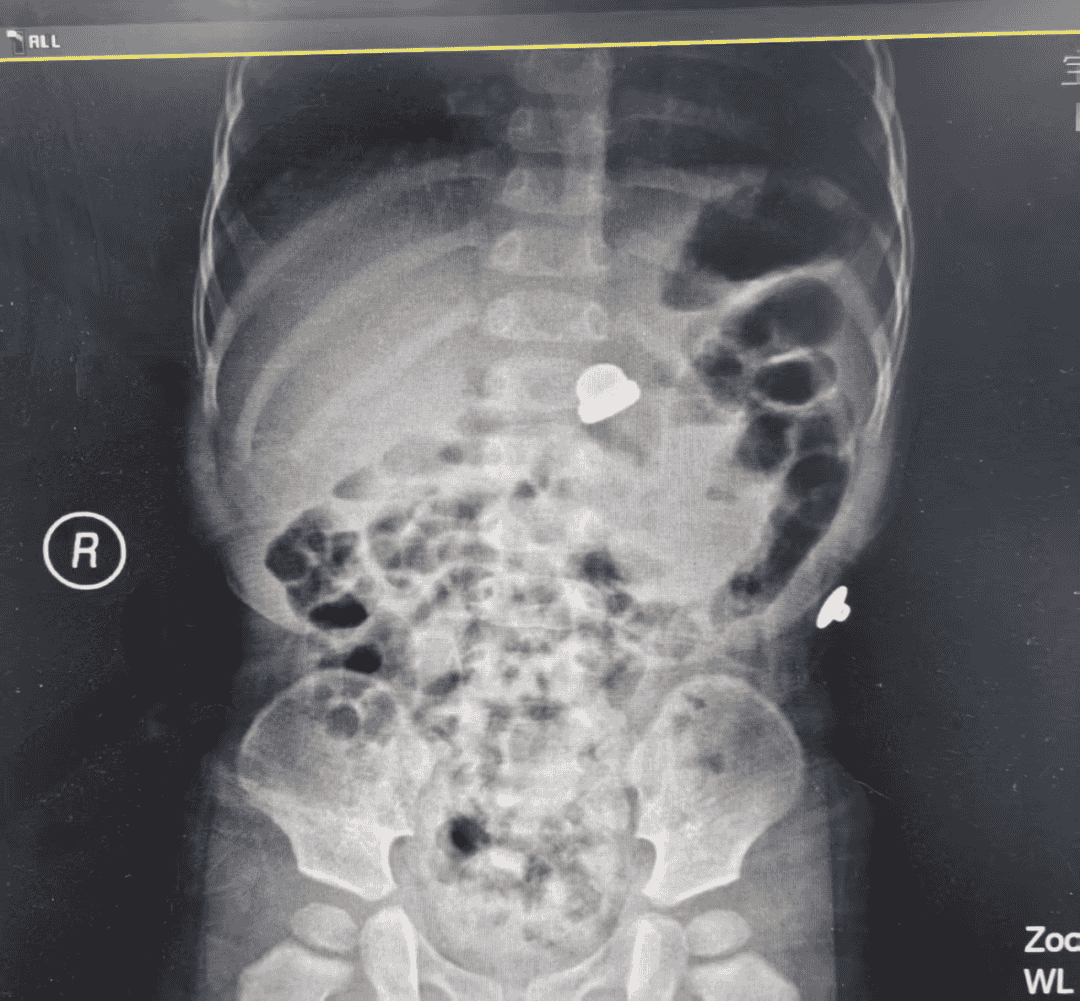

孩子入院后,不但哭闹不止,而且有恶心症状,医护人员迅速完善了影像学检查,发现患儿胃内有一枚螺帽状异物。时间就是生命,医护团队迅速集结。“该异物形状特殊,可能会造成消化道黏膜破裂,引发大出血等严重并发症。”参与会诊的一名医生说。

“鉴于异物密度大,形状不规则,且患儿只有1岁,不容易配合,最安全的办法是在全麻下行胃镜异物取出术……”术前讨论中的专家如是说。

手术方案确定后,医护人员迅速完善了术前准备,麻醉医生凭借丰富的经验,为孩子实施了精准麻醉,确保手术过程既安全又无痛。随后,消化营养科医生娴熟的运用胃镜小心翼翼探入孩子的上消化道,在清晰的视野下,准确锁定了异物位置,但螺丝帽表面光滑,用器械抓取很有难度,这并没有难倒技术高超的医护团队,医生巧妙地使用特殊器械,仅仅用时3分钟,就将这枚金属螺丝帽完整取出。